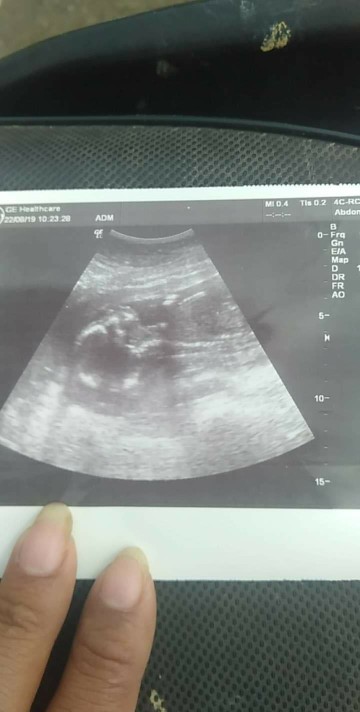

17​ w​ ค่ะ